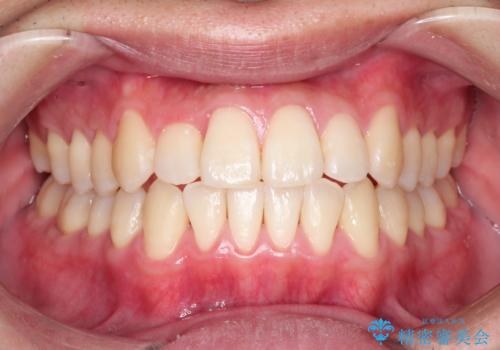

全体的ながたつき ワイヤーによる抜歯矯正で整った歯並びへ